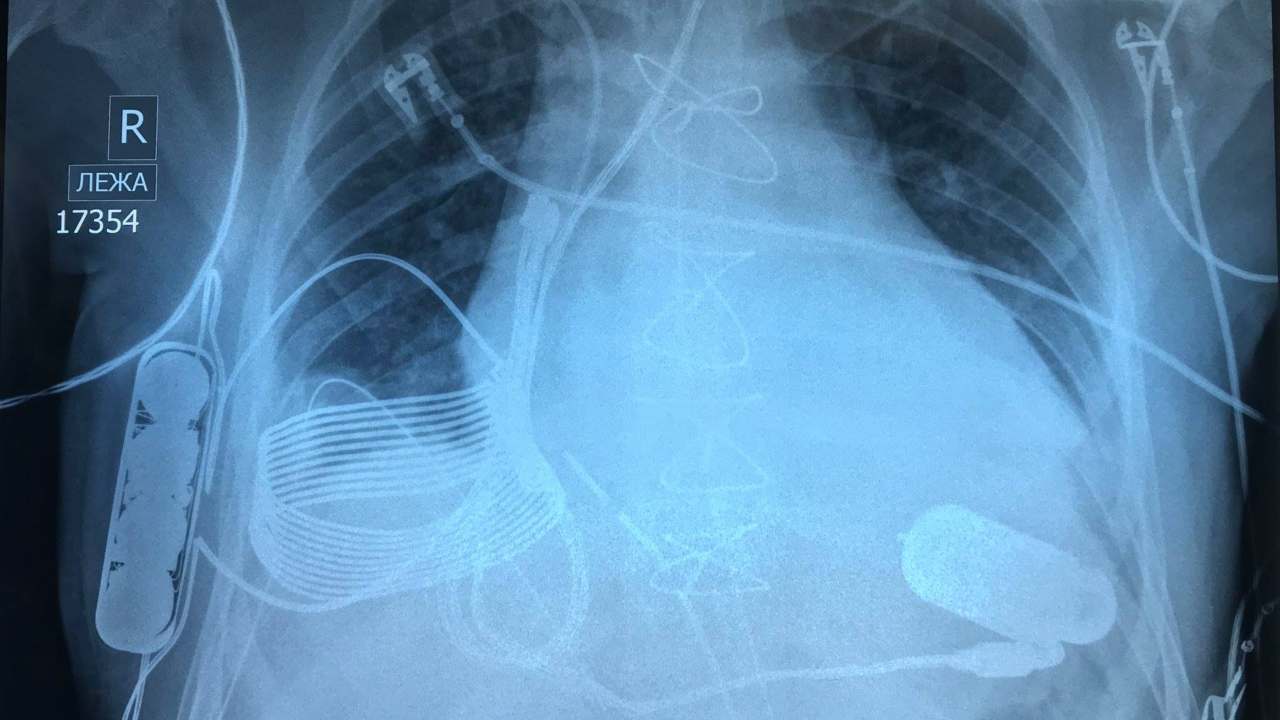

gone by since the first mechanical heart pump — the ventricular assist device — was implanted into a patient whose heart couldn’t pump on its own. Countless lives have been saved by the device since then. One of those patients is a 24-year-old man, Ismail Turnsunov, who was implanted with a heart pump a few weeks ago after being rushed into the hospital with end-stage heart failure. What makes this implant unique is how the device charges up. It requires no wires or charging ports to be connected directly, and can be charged wirelessly. With this feature alone, the device eliminates one of the biggest drawbacks of VADs, which mean an instant heart attack if it fails a patient. [caption id=“attachment_6077901” align=“alignnone” width=“1280”] The three-part bionic heart implant in an X-ray. Image credit: Facebook/Leviticus Cardio[/caption] Usually, a VAD needs to be plugged into a power outlet or an external battery via a hole in the patient’s abdomen. It is absolutely necessary for all patients fitted with a heart pump to carry an extra pair of batteries in case one runs out of power. Another major drawback is the exposed hole through which the power cord runs out of the body — an unsafe, risky gateway for infections. Patients have to alert and be attentive to every little symptom to run to a specialist at the drop of a hat. But Turnsunov’s implant doesn’t require a power cord at all. It uses a wireless charging system built by Israeli technology company Leviticus Cardio.

The instrument has an inductive coil, battery, and an internal controller, which are all implanted into Turnsunov’s chest. The device can stay powered for roughly eight hours from a single charge. When it needs to be recharged, Turnsunov has to put on a vest which has a built-in external device and coil to charge the inner coil using an electromagnetic field. The device comes with a wrist monitor for Turnsunov to track his VAD and battery. In case something in the wireless charging system fails, there currently isn’t a back-up wired option. However, the patient hasn’t needed to use it since his surgery several weeks ago.